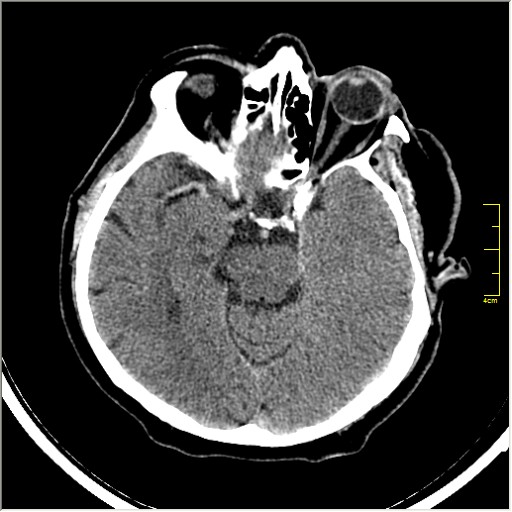

Пациентка Д. 64 года. Поступила с диагнозом ОНМК ???, жалобы на онемение и слабость в левой половине тела.

Ответ: Обратите внимание на правую среднемозговую артерию (MCA); М1 сегмент гиперденсен; сравните с другой стороной.

Этот признак называется [Dense MCA sign]; за счёт наличия тромбоза в её просвете. Этот признак является одним из ранних указующих КТ признаков при ишемическом инфаркте головного мозга. Более подробно об этом вы можете прочитать здесь: http://www.radiologyassistant.nl/en/483910a4b6f14.